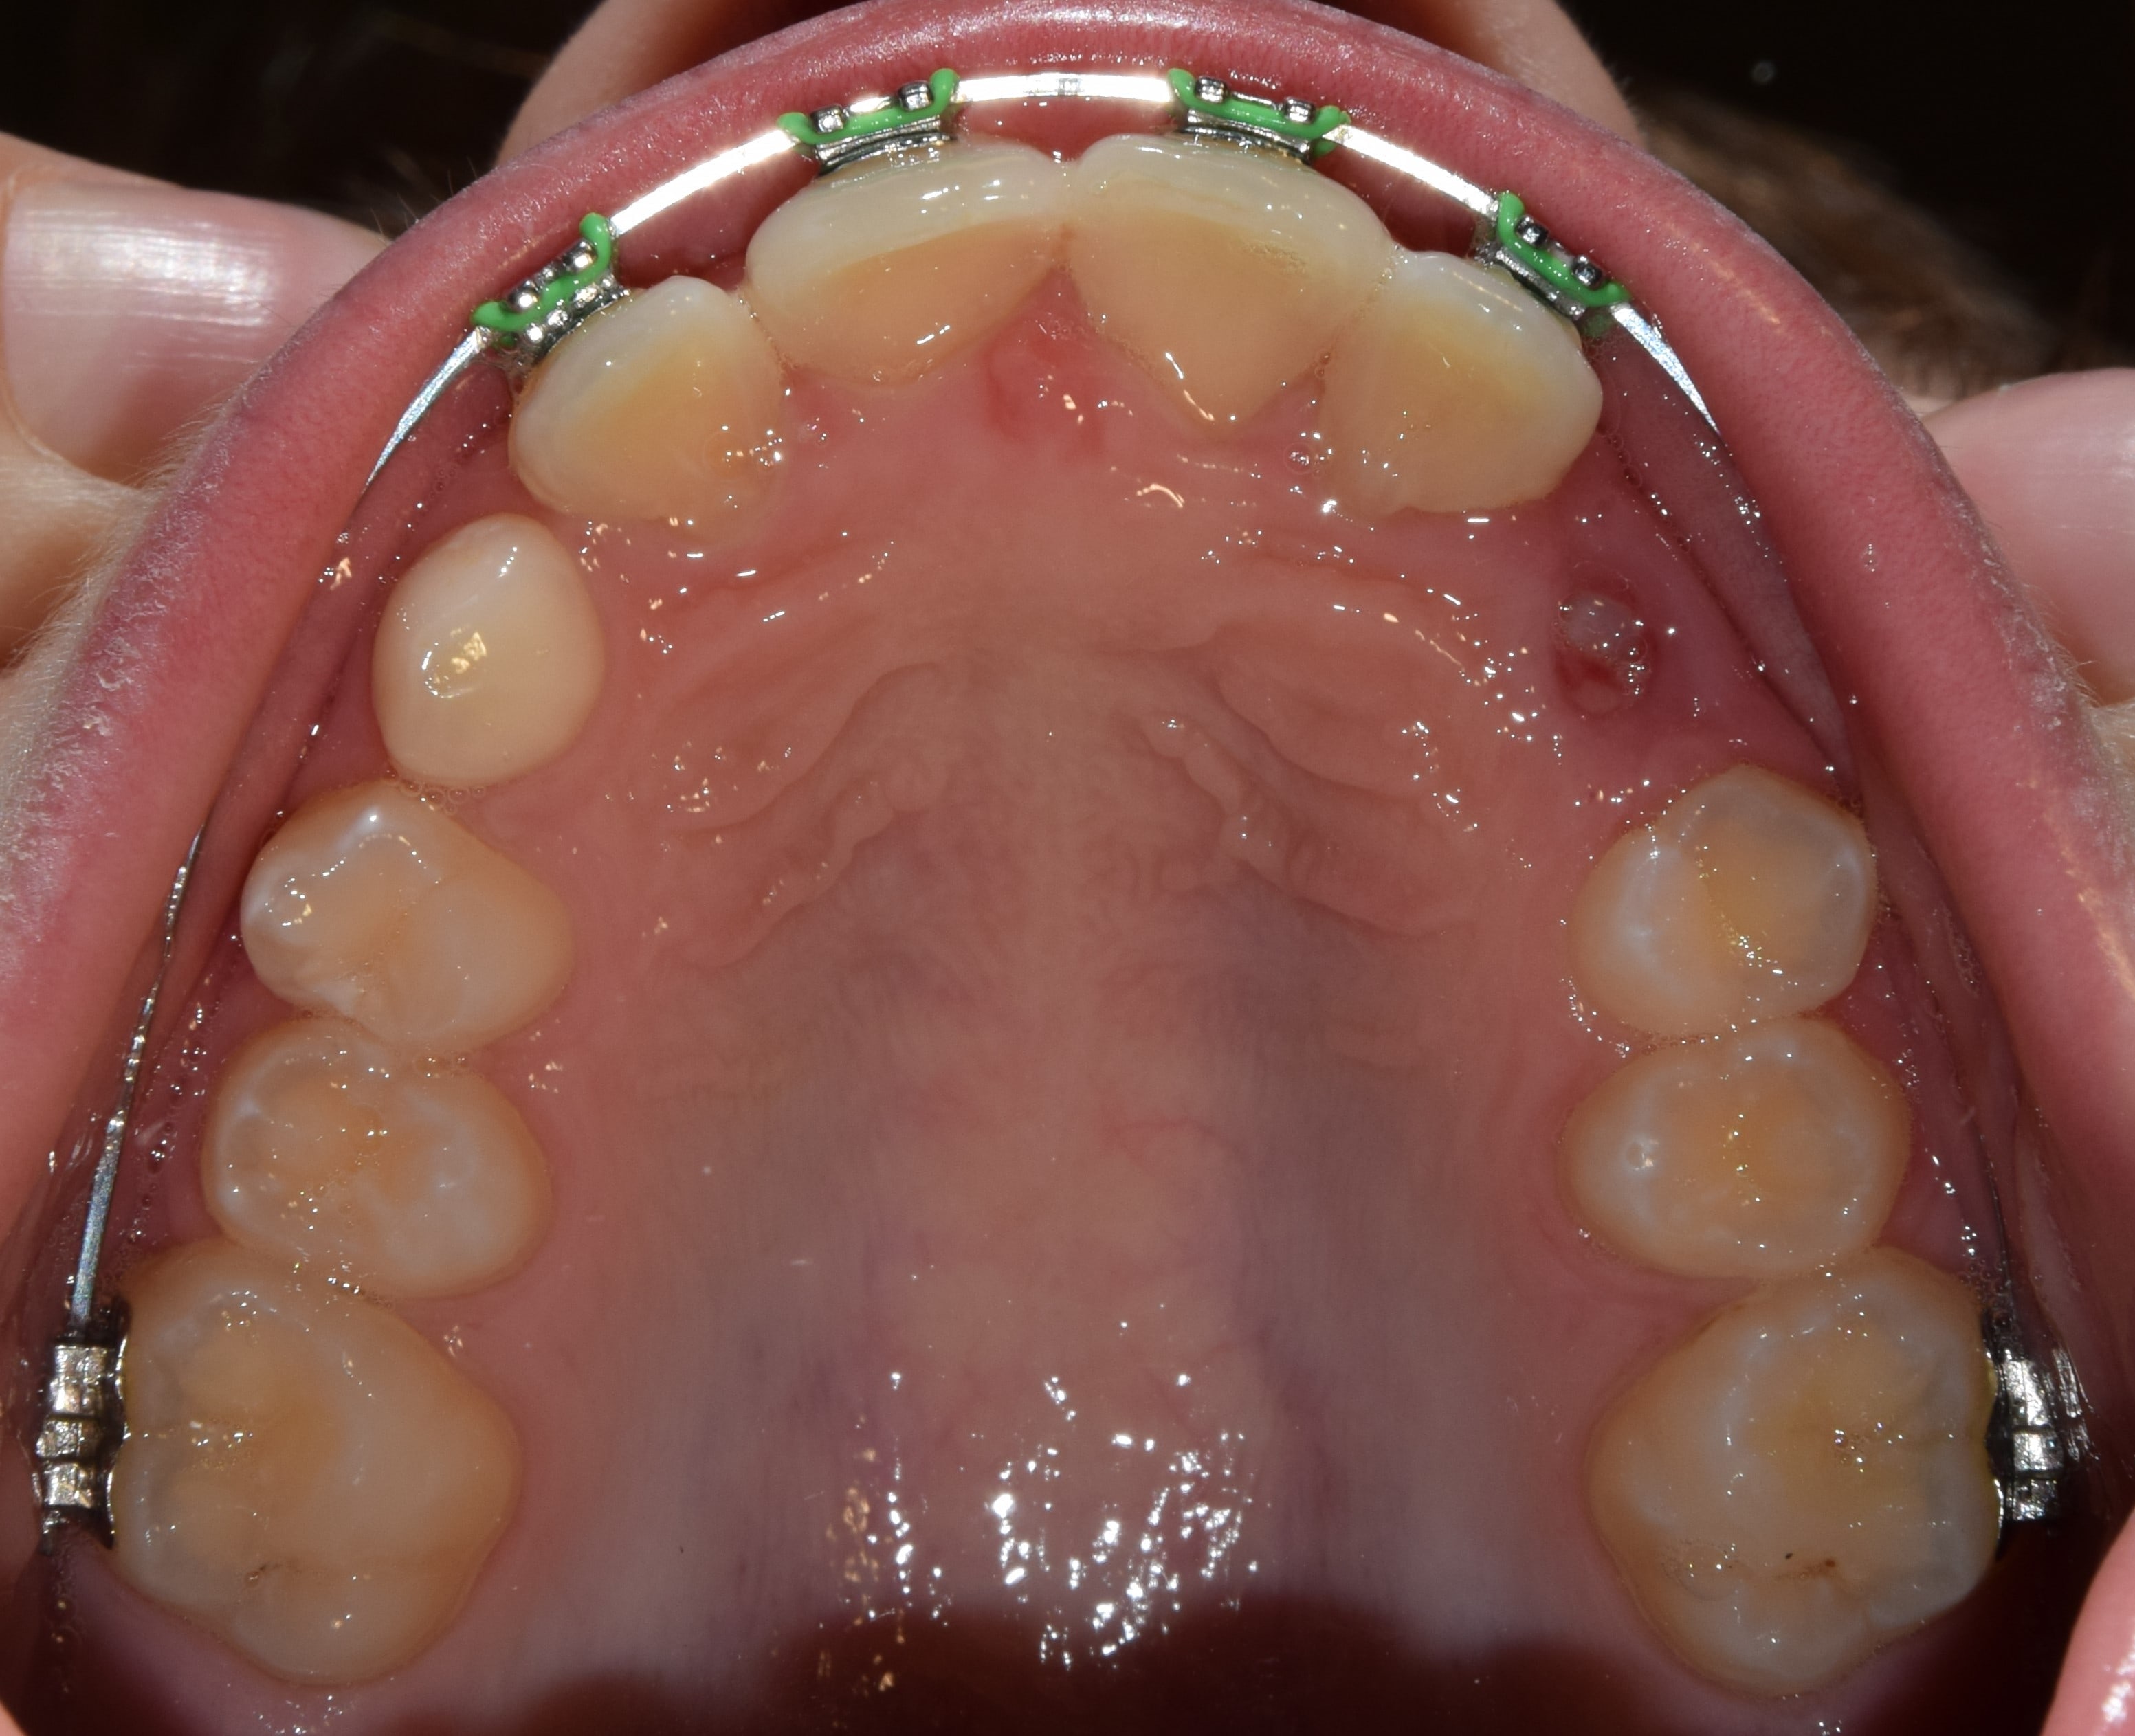

Hyrax

Fiatalkorban a felső állcsont tágítására alkalmas rögzített fogszabályozó készülék. Működése a felső állcsont közepén található csontvarrat (sutura palatina mediana) megnyitásán alapszik. Ilyenkor a két állcsontfelet távolítjuk egymástól. A hyrax maradófogazatban a felső első kisőrlőkön és első nagyőrlőkön rögzül, vegyesfogazatban pedig az első maradó nagyőrlőn és a tejőrlőkön (esetleg tej szemfogon). A vegyesfogazati hyrax készülhet fémből, vagy akrilátból (ez a splint hyrax). A hyrax közepén, a szájpad mélyére süllyesztve található egy csavar, amelyet a pácienseknek, szülőknek otthon kell tekerni. Fiatalkorban (7-9 év) ez 3 naponta 1 tekerést jelent, míg később (9-12 év) naponta 2 tekerést. A készülék működése során a felső állcsont tágul, a mosoly szélesedik, a torlódások spontán oldódnak, és a felső metszőfogak között rés keletkezik (ez idővel magától zárul). A felső állcsont tágulásával az alsó állcsont gyakran spontán előrehelyeződik (megoldva ezzel pl. egy disztálharapást). Átjárhatóbbá válnak a légutak, javul a szervezet és az agy oxigenizációja, ezzel a gyerkőcök alvása, kipihentsége, koncentrációja. Általam sokat használt és kedvelt készülék a hyrax. Fontos megjegyeznem, hogy a fent leírt, ijesztően hangzó mozgatások a pácienseim beszámolói alapján semmilyen fájdalommal nem járnak, és bár drasztikusnak tűnhet a folyamat, a gyerekek által egyik legjobban tolerált készülék. Kezelés hossza: 7-12 hónap. Kontrollok gyakorisága: az első 2-3 hétben hetente, később 4-8 hetente. A kezelés befejeztével vagy Goshgarian kerül fel az eredmény megtartására, vagy teljes rögzített fogszabályzó ragasztásával folytatódik a terápia.

Sutura palatina mediana

A felső állcsont közepén elhelyezkedő csontvarrat. Fogszabályozási jelentősége, hogy a még nyitott állapotban lévő csontvarrat mentén történik a felső állcsont tágítása (hyrax). Ez a varrat kb. 12-13 éves korra elcsontosodik, és ezután kizárólag bonyolultabb készülékek segítségével nyitható újra, vagy szájsebészeti úton. A sutura palatina mediana mentén történt felső állcsont tágítás ténylegesen a felső állcsont alapját szélesíti, tehát nem csak a fogakat mozgatjuk a tágítás során. Ez a legkívánatosabb módja a tágításnak.